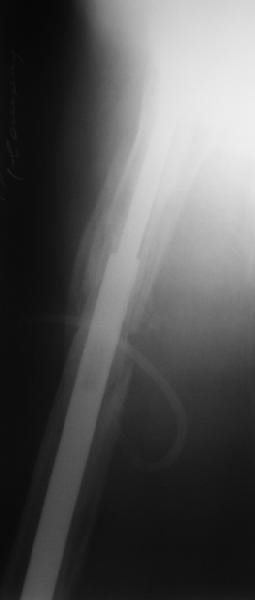

rs> ° distal fixation of the nail is based near only on two

rs> screws : are they sufficient to secure a good stability before fracture consolidation?

I'd say yes because we use same 6 mm screws for femoral nailing and allow immediate weight-bearing regardless of fracture pattern.